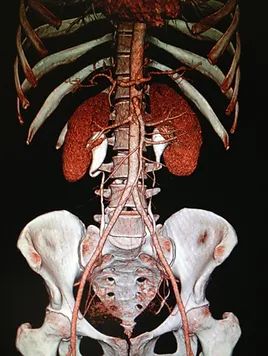

A hormone-secreting tumour that can occur in the adrenal glands. Phaeochromocytomas usually develop in the small glands on top of the kidneys (adrenal glands). They most commonly affect people between the ages of 20 and 50, but can occur at any age. Because of hormones secreted, symptoms include high blood pressure, sweating, rapid heartbeat and headache. Surgery to remove the tumour is usually required.